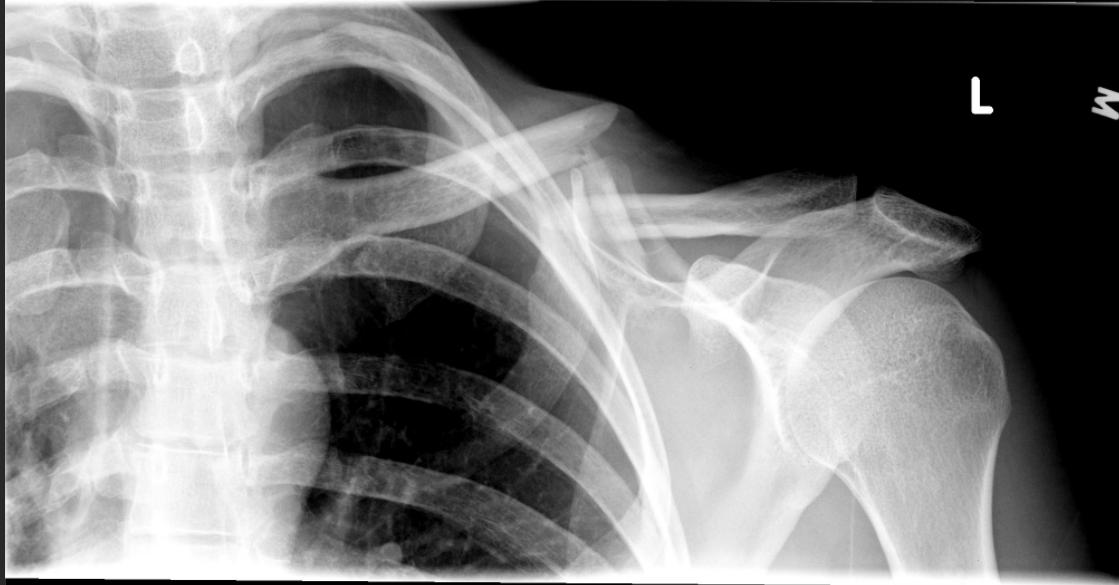

完全骨折

锁骨骨折吃什么食物最好,锁骨骨折怎么绑绷带视频

骨折端向上凸起,可能刺穿皮肤变为开放性骨折